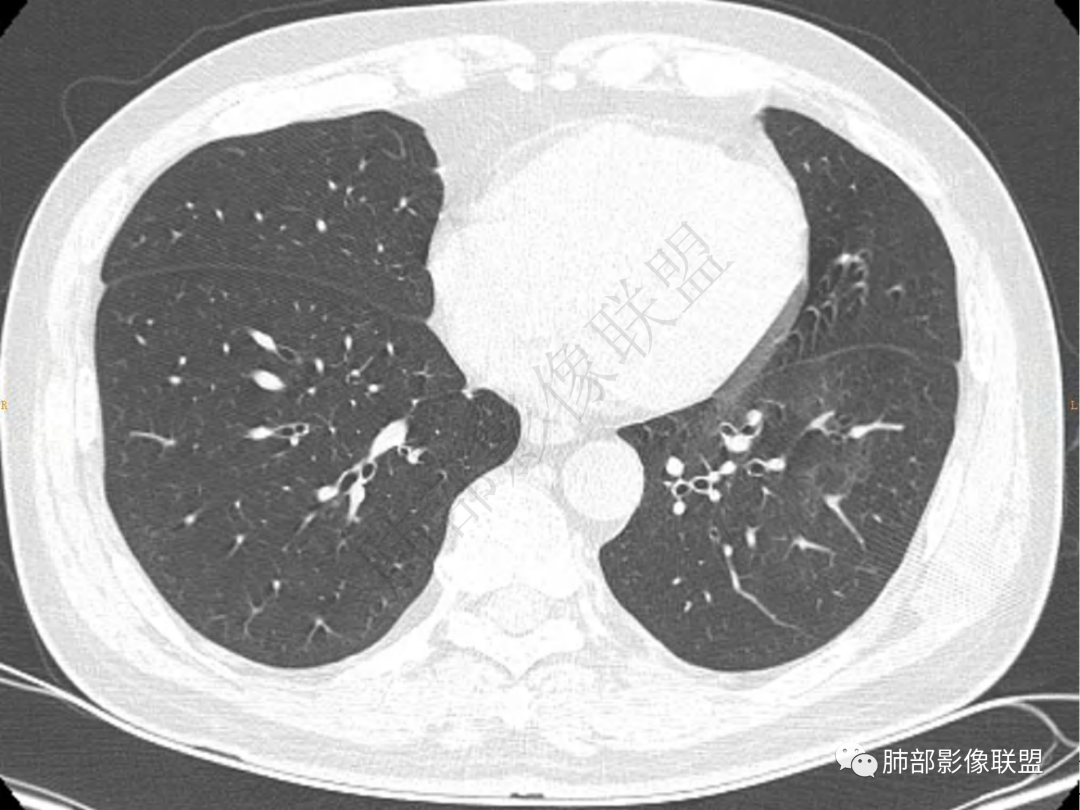

1.中年男性,咳嗽咳痰20余天,间断咯血2周

2.左肺下叶团片影,跨背段及内前基底段,实性部分类椭圆形,密度不甚均匀,可见毛刺及棘状突起,未见典型分叶及胸膜凹陷。病灶上下缘可见相应肺段支气管旁进侧出,管壁轻度增厚,未见狭窄阻塞。

3.周边较大范围磨玻璃影,边界相当模糊,小叶增厚明显。注意叶裂另一侧、左肺舌段亦可见磨玻璃影及增厚的小叶间隔。未见明确卫星病灶。

4.实性部分不均匀环形强化并显示一小范围低密度坏死区或空洞。较之肺窗,整体纵隔窗范围较小,提示病灶并不十分密实。抑或为不同时段图像。

5.双肺门及纵隔未见增大淋巴结。未见胸腔积液。